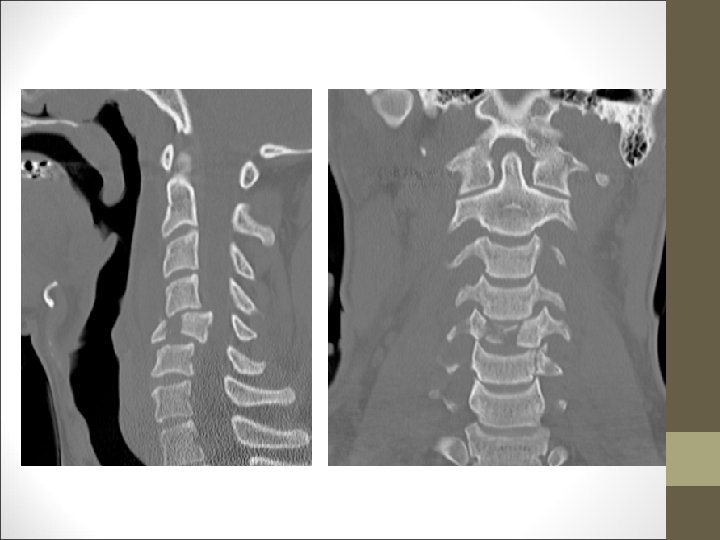

FACULTAD DE MEDICINA DEPARTAMENTO DE CIRUGÍA NEUROCIRUGÍA ¿Qué harías? TAC Cervical

TC Desplazamientos de fragmentos óseos ¿Algo mas? FACULTAD DE MEDICINA DEPARTAMENTO DE CIRUGÍA NEUROCIRUGÍA RM Desplazamientos discales y lesiones ligamentosa

¿Primer paso en el tratamiento? Reducción Cerrada Tracción cervical FACULTAD DE MEDICINA DEPARTAMENTO DE CIRUGÍA NEUROCIRUGÍA Evaluación de estabilidad segmento C 3 -C 7 : -Daño neurológico -Daño importante del complejo ligamentario -Desplazamiento anterior de un cuerpo > 3, 5 mm (20%) -Angulación de vértebras adyacentes de más de 11º -Rotura ligamentosa posterior importante -Lesión del disco